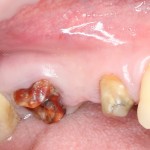

Другие «радикальные методы» не дают такого качественного заживления костной раны даже при использовании барьерных мембран для закрытия окна в субантральное пространство (рис 29):

Рисунок 29. Фотография области операции через 4 месяца после синуслифтинга. Создание доступа в верхнечелюстную полость проводилось шариковым бором и, как результат, окно доступа полностью не заживает.